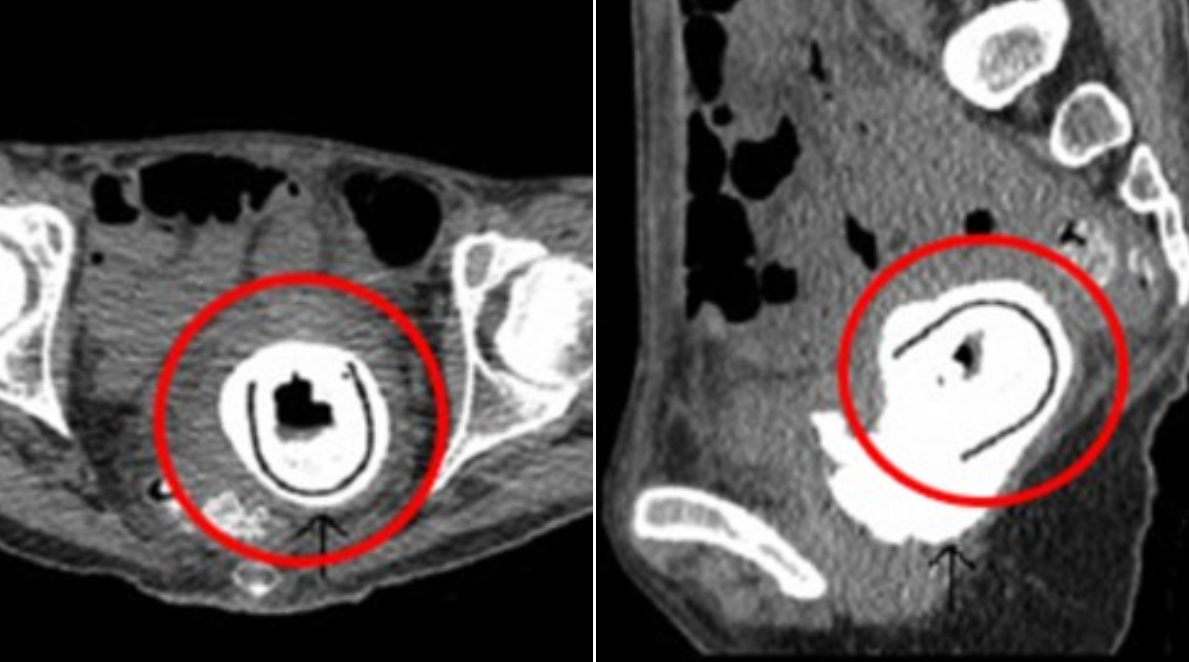

6. Riktig action – upp i baken

Det dyker tydligen upp många konstiga saker i rumpor. Frågan är dock om inte en actiondocka är bland det underligare?